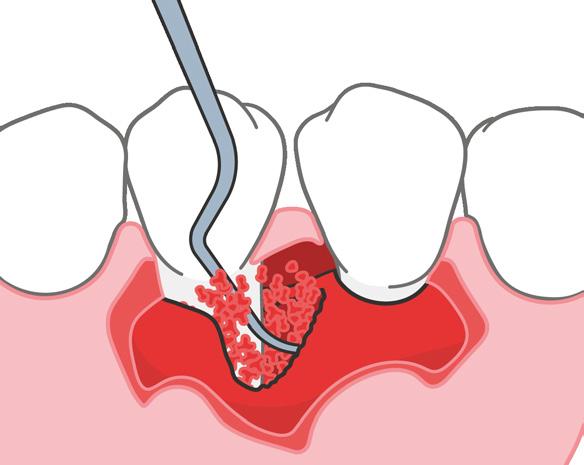

Las lesiones periapicales se encuentran entre las lesiones patológicas más comu nes en el hueso alveolar.2 Este tipo de le siones provoca defectos óseos y, cuando son grandes, el organismo no es capaz de regenerar hueso nuevo para rellenar los. Entonces el tejido conectivo invade el defecto óseo y afecta a los resultados clínicos.3

Injertar el defecto con un sustituto óseo y cubrirlo con una membrana reabsorbi ble puede ayudar al organismo a corregir

el defecto. En los tratamientos endodón ticos regenerativos para defectos gran des, como con la terapia periodontal regenerativa, los dentistas usan hueso autógeno y biomateriales, o una mezcla de ambos.

Microcirugía periapical regene rativa

La microcirugía periapical regenerativa emplea los principios fundamentales de la endodoncia, la periodoncia y la odonto logía oral y restauradora. Por lo general, el objetivo del tratamiento es eliminar todos los posibles factores causantes de lesio nes periapicales, reparar la arquitectura del tejido periapical perdido y conservar la estructura y la anatomía de la raíz y de los tejidos blandos. También es importan te prevenir la recidiva de la enfermedad a largo plazo.